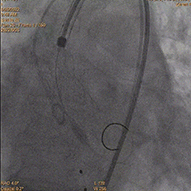

术中影像:

行冠脉PCI术

直头导丝顺利跨瓣

瓣膜释放至工作位

瓣膜释放至理想状态压差为2mmHg